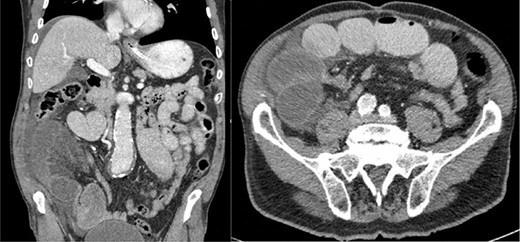

An 80-year-old man, with a history of peripheral arterial disease, presented with acute abdominal pain, nausea and vomiting. On physical examination, the patient was afebrile with a blood pressure of 141/79 mmHg and pulse rate of 51 beats per minute. Abdominal examination revealed a tender palpable mass in the right lower quadrant. His white blood cell count was 10.0 x 109/l, and the C-reactive protein level was <1 mg/l. Ultrasonography revealed short bowel distension. A complementary computed tomography (CT) was performed and showed a closed loop short bowel obstruction in the right lower quadrant and ascites (Fig. 1).

CT: demonstrates closed loop short bowel obstruction with dilated small-bowel loops and ascites